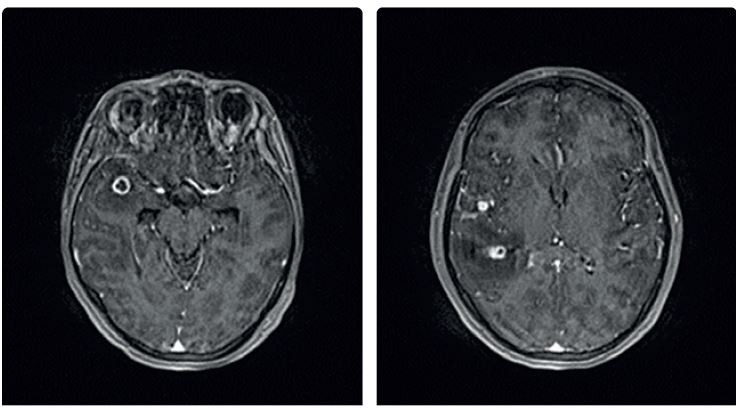

Obr. 2 Radiologický nález pacienta s MDR/RR TB. Rozsáhlý oboustranný radiologický nález, kaverny v obou plicních vrcholech (archiv autora) MDR/RR TB – multirezistentní, resp. rifampicin rezistentní tuberkulózaDiagnóza tuberkulózy se opírá o anamnézu, klinické symptomy, patologický radiologický nález a zásadní význam má bakteriologický průkaz patogenu ve vyšetřovaném materiálu. Radiologický nález u TB bývá charakteristický, ale nikoli specifický (obr. 2). Radiologicky může tuberkulóza imitovat jakékoliv plicní onemocnění. Nicméně zadopřední skiagram hrudníku doplněný o boční projekci je základním vyšetřením u plicní i mimoplicní TB. Pokud u pacienta s patologickým radiologickým nálezem není ve sputu M. tuberculosis jednoznačně prokázáno, doplníme k upřesnění nálezu vyšetření výpočetní tomografií (CT) s vysokým rozlišením (HRCT hrudníku). V případě podezření na mimoplicní TB indikujeme zobrazení ostatních tkání a orgánů – magnetickou rezonanci (MR) centrálního nervového systému (CNS), skiagramy či CT, ev. MR kostí, vylučovací urografii, CT břicha apod. (obr. 3).Obr. 3 Magnetická rezonance CNS. Postižení mozku tuberkulomy. Pacientka léčená přípravky anti‑TNF pro psoriázu s diagnózou TB plic, pleury a CNS (archiv autorky) CNS – centrální nervový systém; TNFα – tumor nekrotizující faktor alfa; TB – tuberkulóza